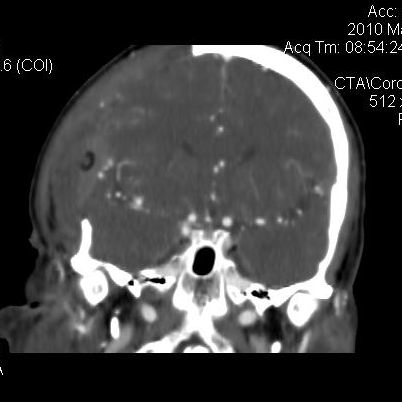

男.60岁,渐进性意识不清,ct检查双侧额颞顶部硬膜下血肿,开颅术后行脑血管cta,大脑中动脉起始部见一瘤状血管扩张。请各位老师留下宝贵意见

太常见了,报动脉瘤就可以

符合动脉瘤表现。

符合动脉瘤表现。

动脉瘤。

颅内动脉瘤。

小动脉瘤

典型

符合动脉瘤的表现

动脉瘤

符合动脉瘤表现。

小动脉瘤

典型